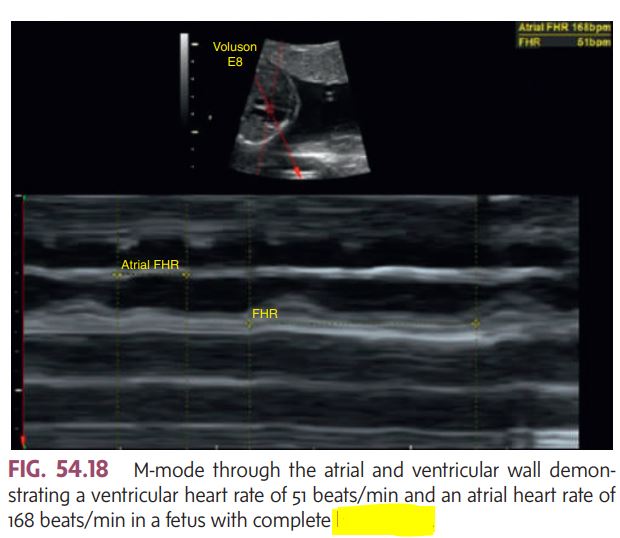

Two-dimensional and M-mode image demonstrating

pericardial effusion.

The fetal heart must be monitored to rule out congenital _________ (Fig. 54.18) and pericardial effusion.

heart block